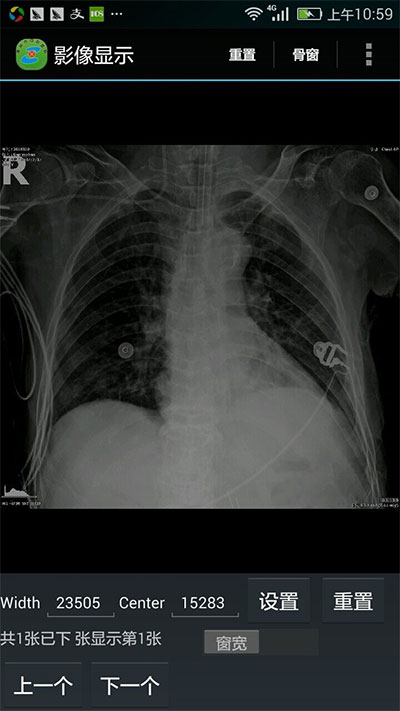

通过技术人员近一年的开发实践,中心医院掌上医疗项目开发完成,实现了病人全信息的查询功能:能展示病人的体温单、医嘱单、入院记录、病程记录、手术记录、出院记录、检验检查报告单、医学影像、窗位变换等。

湖州中心医院一直致力于医疗信息化建设,加快医生诊断、检查流程,提高病人就医体验,为了使医生能够随时了解并掌握病人的实时信息,医院决定引入掌上医疗,并为医生配备了业务手机,方便医生及时获取病人的诊疗数据。但dicom数据的读取一直以来难以移植到移动端,尤其图像处理这一部分的开发是比较有难度的,目前业界在移动端上连接pacs和展示医学影像的控件就数leadtools比较成熟,能够在手机上显示医学影像文件、更改窗位、连接pacs系统、显示病人信息。大大减少开发难度,节省开发成本。

窗位变换:

窗位变换前 窗位变换后